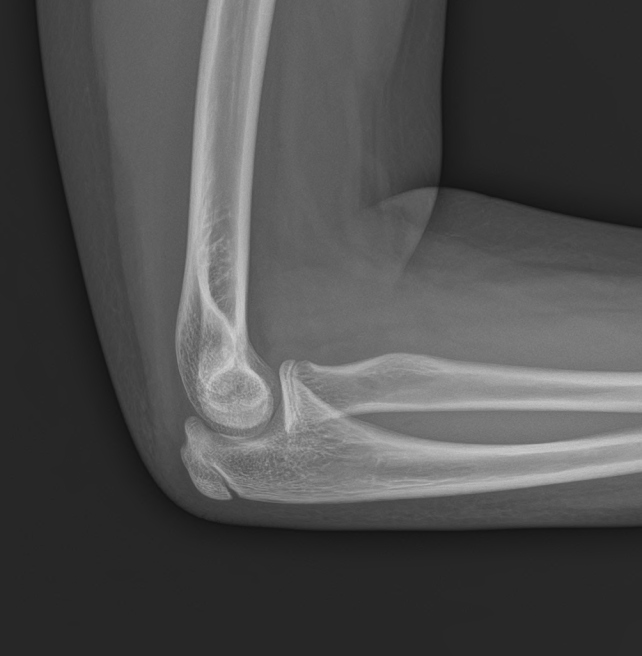

뼈나이로 빠르게 확인을 먼저 해봐야겠다.

"사진 찍고 다시 한번 봐드릴게요."

뼈나이는 언뜻 봐도 12세를 훌쩍 넘었다.

아이는 실제 나이는 만 9세이지만,

몸의 발달 생체 시계는 또래보다 3살 이상 빠르게 돌아가고 있다.